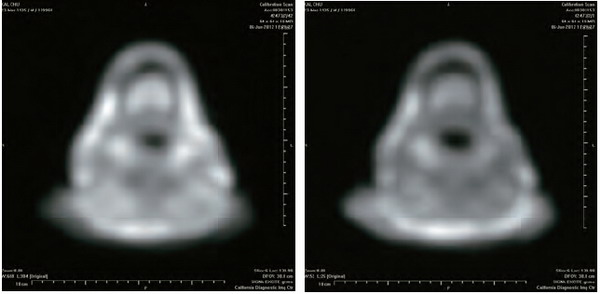

红外线热感应仪探测开初仁波且拙火高温

这是从实况录像中截取的照片,是开初仁波且在修摊尸拙火定时用红外线热感应摄影仪拍摄的。画面上热感应仪探测出三种温度:一,这一刻开初仁波且身体的最低温度:华氏77.9度;二,开初仁波且身体的最高温度:华氏197.4度,高温发出位置在肚脐下密轮处(丹田),鲜红色部位。三,开初仁波且身体平均温度:华氏164.1度。华氏197.4度,也就是摄氏92度,这已是快要将水煮开、肉煮熟的温度!【详见《千年难见的真佛法现前》DVD实况录像】